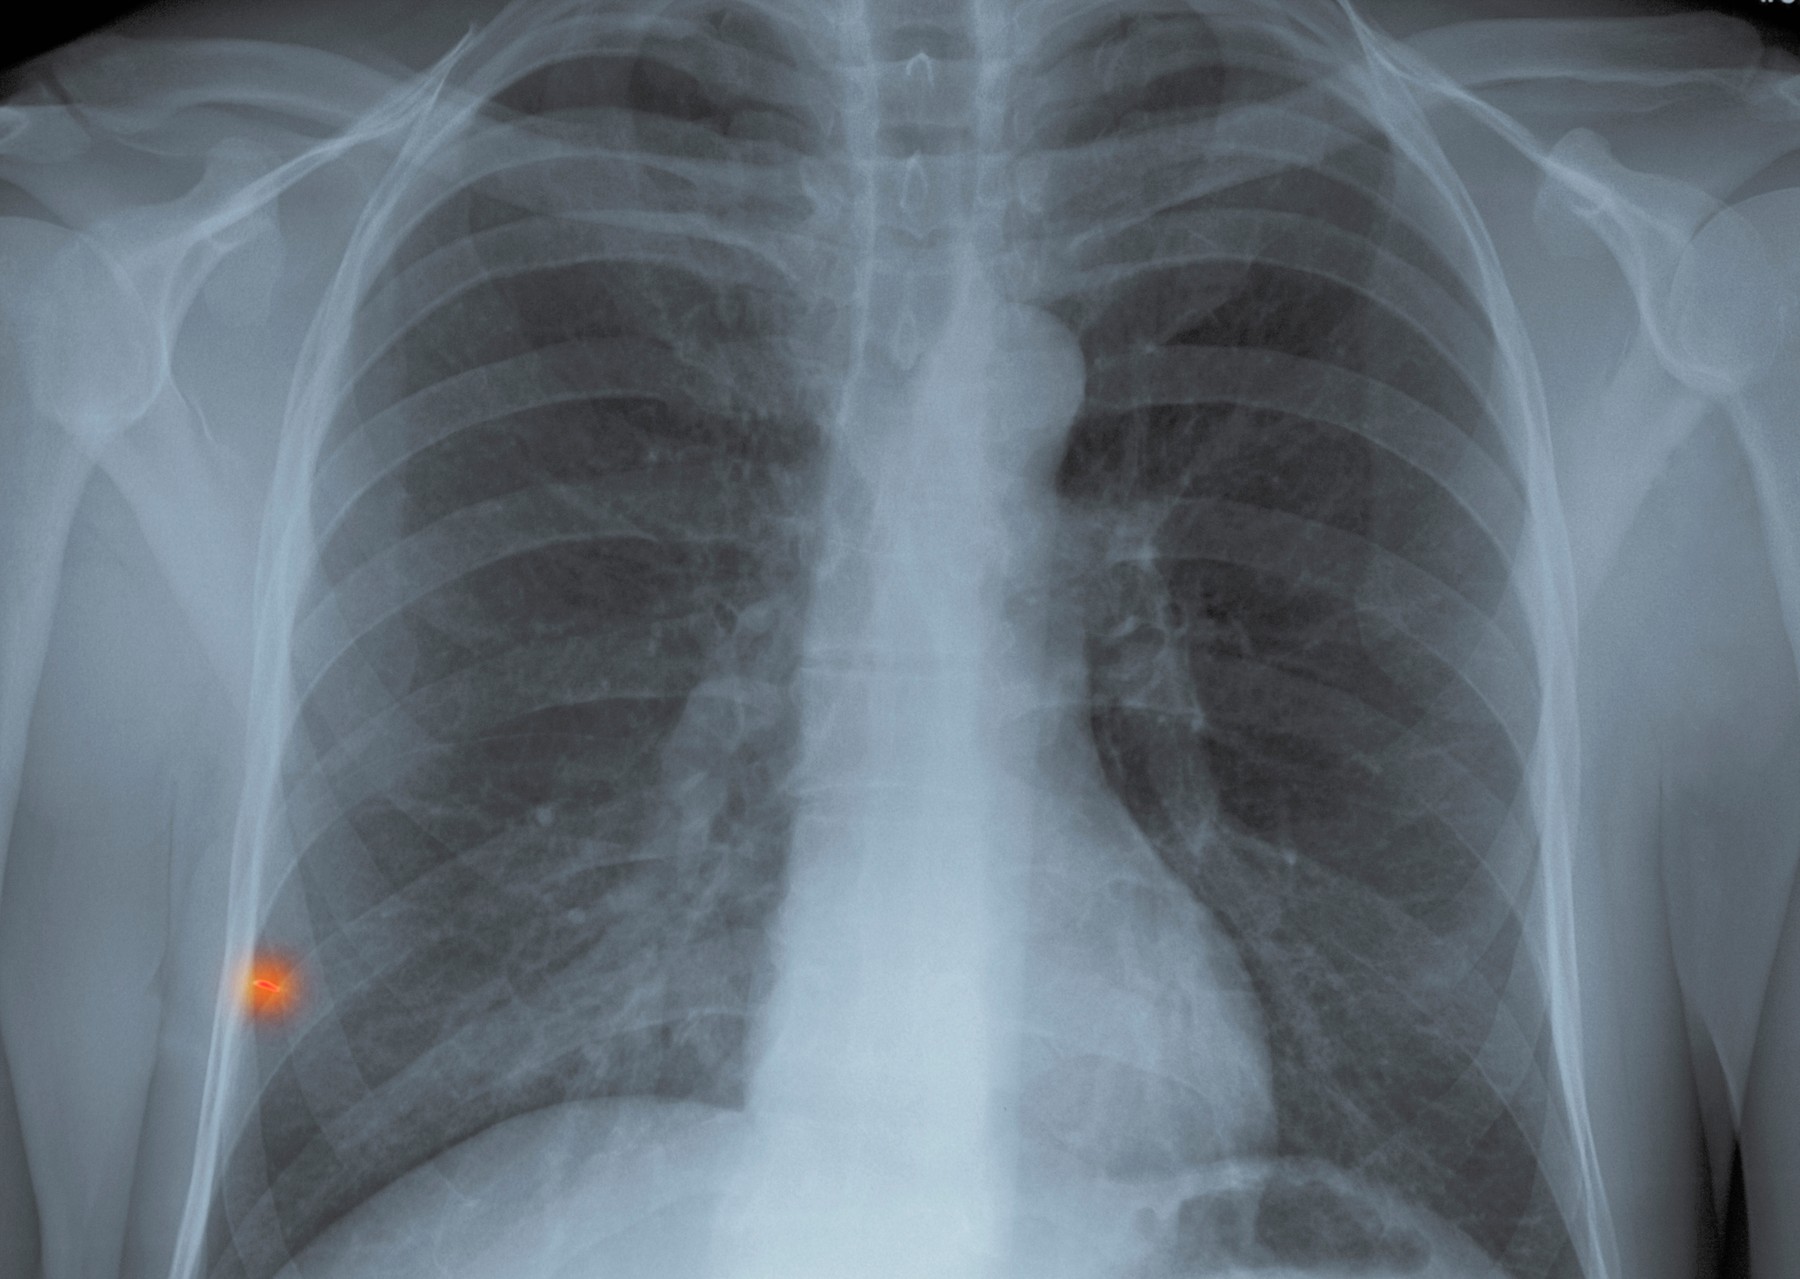

Foto: Arhiva/Privatna arhiva Foto: Arhiva/Privatna arhiva Foto: Arhiva/Privatna arhiva Dr Lukić ima najbolji savet ako upalu pluća lečite kod kuće autor: Božica Luković Zdravlje 03. dec. 2020. 09:58 > 03. dec. 2020. 09:58 0 Podeli vest: Pulmolog Srđan Lukić detaljno je pisao o upali pluća koju izaziva kovid 19, kao i o tome kako se možete lečiti od kuće ukoliko dobijete pneumoniju, s obzirom na to da lekari sve češće na kućno lečenje šalju i pacijente pod upalom. Podeli vest: Oglas Doktor Lukić je inače jedan od učesnika akcije Nova.rs Struka protiv korone u okviru koje smo okupili najeminentnije stručnjake da pokušaju da reše sve dileme koje imate u vezi sa koronavirusom, a niste imali koga da pitate.On će danas odgovarati na pitanja naših čitalaca, a u međuvremenu je objasnio i šta da radite ukoliko upalu pluća izazvanu kovidom morate da lečite kod kuće, koji simptomi su znak za uzbunu i kada se obavezno moramo javiti lekaru.Njegovu objavu prenosimo u celosti:"Osim što srpski protokol za lečenje kovida eksplicitno kaže da za blage oblike bolesti, bez upale pluća, NE treba davati antibiotik, isto kaže i da bi SVI pacijenti kod kojih je registrovana upala morali biti hospitalizovani, što u predstojećim danima verovatno neće biti slučaj.Ovde ću pokušati da vam približim tu kovid upalu pluća kako bi se smanjio nivo straha kod ljudi koji će ostati da je leče kod kuće, i pomoći im da je isprate adekvatno, koliko je to već moguće u kućnim uslovima. Ono što prvo treba reći je da NE postoji lek koji je može sprečiti.Dakle kada se kovid upala pluća javi kod nekoga treba da zna da ništa nije moglo da je spreči. Zašto se kod nekoga javi, a kod nekoga ne, to još uvek ne znamo, i ne možemo unapred predvideti. Svako ko se zarazi SARS-CoV-2 virusom ulazi u tu svojevrsnu lutriju - pneumonija ili ne.Većina ljudi koji dobiju kovid će proći bez upale pluća. Isto tako i većina sa upalom pluća će proći bez komplikacija. I isto kao što ne možemo znati kod koga će se razviti upala a kod koga ne, ne možemo pretpostaviti ni da li će doći do komplikacija, ako dođe do upale pluća.To je razlog zbog koga bi svaki pacijent sa upalom pluća trebalo da bude hospitalizovan, da bi se pratio razvoj mogućih komplikacija. Po protokolu više puta dnevno se prate vitalni parametri i opšte stanje kako bi se odmah reagovalo u slučaju pogoršanja (i dalje bez antibiotika). Snimak pluća - ilustracija; Foto: Callista Images / Cultura RF / Profimedia | Snimak pluća - ilustracija; Foto: Callista Images / Cultura RF / Profimedia E sad, šta se dešava kod upale pluća - dolazi do zahvatanja plućnog tkiva, i to ne samo virusom, nego i od strane ćelija našeg imunog sistema. Pluća su organ koji, da to tako kažem, može enormno da poveća svoj "rad", ako za tim postoji potreba. Tako je i kod upale pluća.Mnogi ljudi žive decenijama sa samo jednim plućnim krilom. Kod upale pluća ako je zahvaćeno recimo manje od 50% pluća, ostatak koji je zdrav će preuzeti funkciju i često oboleli neće ni primetiti da nešto nije u redu. To se dešava kod asimptomatskih pacijenata.Ukoliko se progresija bolesti zaustavi na tom nivou, ili čak i na nivou gde pacijent ima blažu simptomatologiju (npr. brže se zamori u naporu), to apsolutno nije stvar za zabrinjavanje. Problem nastaje u onom momentu kada zdravi deo pluća ne može da kompenzuje celokupni "rad".U tom momentu je potrebno pomoći plućima u njihovom "radu", a prva mera je nadoknada kiseonika, i to pacijent sam ne može da izvede u kućnim uslovima. Ukoliko pluća ne dostavljaju dovoljno kiseonika u krv to onda rapidno pogoršava i opšte stanje nekoga ko nema hroničnih bolesti.Za pacijente koji imaju hronične bolesti manjak kiseonika u krvi vrlo verovatno, pored dodatnog pogoršanja kovida, vodi i u pogoršanje tih hroničnih bolesti, što na još jednom nivou komplikuje situaciju, i vodi ka neželjenom ishodu bolesti.E sad najvažnije - kako prepoznati da je funkcija pluća postala neadekvatna? Najbolje bi bilo ako možete da nabavite pulsni oksimetar, koji meri saturaciju kiseonika na periferiji. Iako su ti aparati često nepouzdani (recimo ne rade na hladnim prstima) ipak mogu da pomognu.Rezultati koje oksimetri pokazuju često veoma osciliraju, pa čas pokažu 97%, čas padnu na 94% i to nije zabrinjavajuće. Za brigu je ako je non-stop ispod 94% uz uslov da je prethodno u toku dana, ili dan ranije, bio preko 95-96% jer neko npr. zbog hronične bolesti stalno ima 90%.Ako nemate oksimetar znaci pada nivoa kiseonika u krvi su sledeći: glavobolja, bledo-plava prebojenost kože i sluzokoža (najpre prstiju i usana), ubrzano disanje, ubrzani rad srca, pad arterijskog pritiska, anksioznost, uznemirenost, konfuzija, gubitak snage pri najmanjem naporu.Naravno, ne treba paničiti ako se javi jedan od ovih znakova pošto su oni nespecifični, i često mogu biti i posledica straha - psihosomatika. Ali ako se javi više njih zajedno, to je onda signal da pluća popuštaju i da je organizmu potreban dodatak kiseonika. Foto: Shutterstock | Foto: Shutterstock Ako vas pošalju na kućno lečenje sa kovid upalom pluća ne treba gubiti glavu. Najvažnije je, kao i kod svake virusne infekcije, da mirujete što je više moguće, i da svu energiju ostavite organizmu za borbu sa virusom. Uzimajte lekove koje vam je dao lekar, uzimajte tečnost.Uzimajte dovoljno hrane, opustite se maksimalno, ako vam posao dozvoljava da radite od kuće - nemojte. Svaki stres, pa i najmanji, može pogoršati bolest. Pustite omiljene filmove i serije, slušajte muziku u kojoj uživate. I nemojte ceo dan misliti o bolesti i mogućem pogoršanju.Najbolje bi bilo da kao što se radi i u bolnici, odredite 3-4 termina u danu kada ćete uraditi evaluaciju znakova i simptoma. Zapišite ih da biste mogli da uporedite, vodite evidenciju. Van toga se bavite opuštajućim stvarima jer TO je zapravo najbolja terapija virusne infekcije. Foto:Roman Lacheev / Alamy / Alamy / Profimedia | Foto:Roman Lacheev / Alamy / Alamy / Profimedia Unapred isplanirajte šta ćete raditi u slučaju da dođe do pojave znakova koji ukazuju na pogoršanje. Sigurno će vam lekar reći gde da se javite u tom slučaju, vi samo pripremite sve unapred da ne biste to radili u brzini jer to može dodatno pogoršati celokupnu situaciju.Kod većine kovid pacijenata sa upalom pluća, bolest će proći bez komplikacija. Ono što je važno je da nakon završenog lečenja još minimum 15 dana provedete u mirovanju i blagim fizičkim aktivnostima, i da se obavezno javite na zakazanu kontrolu, kako vam je već isplanira lekar.Kovid je bolest koja je jedinstvena po mnogo čemu, pa i po tom periodu oporavka, o kome i dalje ne znamo puno, ali znamo da se može javiti prolongirana simptomatologija bolesti koja traje nedeljama čak iako virusa odavno nema u organizmu. I zato ozbiljno shvatite i taj oporavak.NAPOMENA: Ukoliko vam je vaš lekar propisao antibiotik vi ga obavezno uzmite. Ja sam ovde govorio u načelu, o protokolu lečenja kovid. Vaš lekar je taj koji vas leči, ne protokol, i on snosi odgovornost za lečenje - ne protokol.https://twitter.com/srdjl/status/1334385370268655617***Bonus video:https://www.youtube.com/watch?v=--vFFj25UvcPratite nas i na društvenim mrežama:FacebookTwitterInstagram Pulmolog: Pušači imaju teže oblike koronavirusa Zdravlje 0 Korona uništava sluh - lekari iz Niša imaju krunski dokaz Zdravlje 0 Čuvena doktorka objasnila: Greške koje su nas skupo koštale Zdravlje 0 Neobični simptomi kod kovid pozitivnih u Srbiji Zdravlje 0 Zastrašujući snimci skenera pluća od 1. do 15. dana kovida Zdravlje 0 Kako da oporaviš telo ako si preležao kovid 19 Zdravlje 0 dr srđan lukić kovid-19 upala pluća Pratite nas na društvenim mrežama: Koje je tvoje mišljenje o ovoj temi? Učestvuj u diskusiji ili pročitaj komentare Budite prvi koji će ostaviti komentar Pošalji komentar Pročitaj komentare (0)